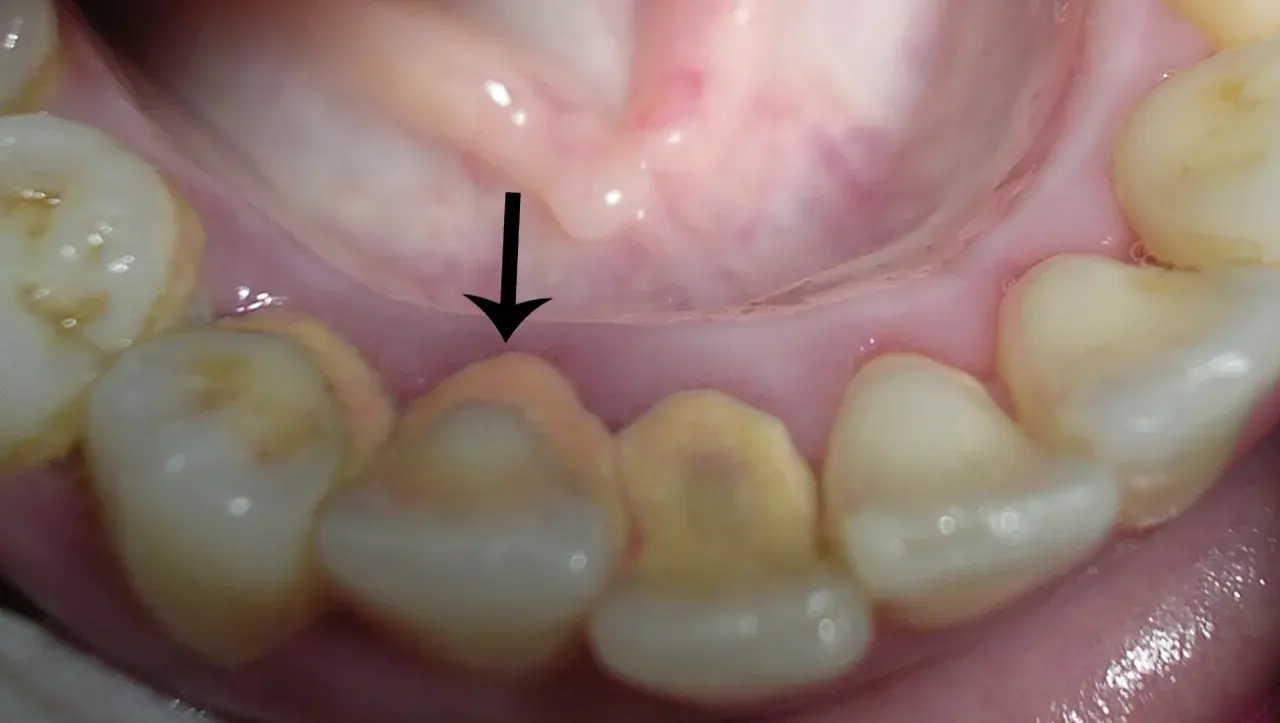

3.ตำแหน่งที่มักเกิด

– มักพบบริเวณขอบเหงือกด้านล่าง (ฟันหน้าล่าง) และด้านแก้มของฟันกรามบน เพราะตรงนั้นมีท่อน้ำลายใหญ่ออกมาดูดซึมแร่ได้มาก